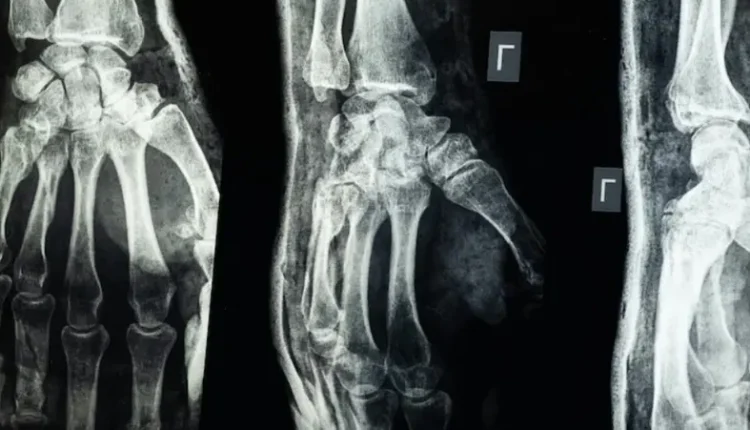

أعلن فريق بحثي في مقاطعة تشيجيانغ شرق الصين عن ابتكار طبي جديد يتمثل في “غراء عظمي” قادر على معالجة الكسور وتركيب الشظايا العظمية خلال ثلاث دقائق فقط، في خطوة وُصفت بأنها اختراق علمي في عالم جراحة العظام، بحسب ما نقل موقع “إن دي تي في” NDTV.

يحمل الابتكار الطبي الجديد اسم Bone-02، وقد استلهم رئيس الفريق الطبي الدكتور لين شيانفِـنغ، فكرته بعد ملاحظته للطريقة التي تلتصق بها المحار بجسور تحت الماء، بحسب ما نقلت عنه صحيفة “غلوبال تايمز”

وأوضح أن هذا الغراء يتميز بقدرته على التثبيت السريع والدقيق حتى في بيئة غنية بالدم، مع ميزة إضافية كونه يُمتَص طبيعياً من الجسم أثناء عملية الالتئام، ما يلغي الحاجة إلى عمليات جراحية لاحقة لإزالة المسامير أو الصفائح المعدنية.

وأكدت الاختبارات المعملية أن Bone-02 نجح في تحقيق نتائج جيدة من حيث السلامة والفعالية. وفي إحدى التجارب، أُجريت العملية في أقل من 180 ثانية (ثلاث دقائق)، بينما كانت طرق العلاج التقليدية تتطلب وقتاً وبحسب الاختبارات المعملية، تمكن الغراء من تحقيق قوة ربط تفوق 400 رطل، وقوة قص تبلغ نحو 0.5 ميغاباسكال، وقوة ضغط تقارب 10 ميغاباسكال. كما أظهرت التجارب على أكثر من 150 مريضاً نتائج ناجحة، ما يعزز احتمالية أن يصبح بديلاً للزراعات المعدنية التقليدية التي تُستخدم في تثبيت العظام. كما يقول العلماء إنه قد يقلل أيضًا من مخاطر العدوى.